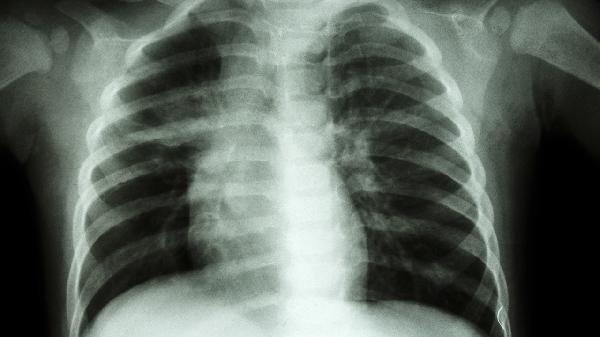

外翻X线表现与测量包括哪些

外翻X线表现与测量主要包括足部力线偏移、跖骨间角度增大、第一跖趾关节半脱位、籽骨位置异常及前足横弓塌陷等指标。

外翻在X线下表现为第一跖骨内翻与拇趾外翻形成的异常力线。通过测量拇外翻角可量化畸形程度,正常值小于15度,超过20度提示病理改变。典型特征包括第一跖骨内侧骨赘形成,第二趾可能发生锤状趾变形。

第一、二跖骨间角在X线正位片上超过9度即为异常。角度增大程度与畸形严重性相关,中度畸形为10-15度,重度可达20度以上。常伴随第一跖骨旋前及第二跖骨头下胼胝体形成。

关节匹配度可通过关节面夹角评估,正常小于7度。半脱位时可见近节趾骨基底向外侧移位,关节间隙不对称增宽,后期可能出现关节边缘骨赘增生或软骨下骨硬化等退行性改变。

籽骨系统位置通过籽骨分级评估,正常位于第一跖骨头下方。外翻时可见腓侧籽骨外移,严重者完全脱位于跖骨间隙。籽骨移位可导致屈拇肌腱力臂改变,加重畸形进展。

通过测量跖骨头连线与地面的夹角评估横弓形态,塌陷时角度增大。X线侧位片可见第二、三跖骨头下沉,可能伴发转移性跖痛症。晚期病例可能出现跖趾关节背侧半脱位。